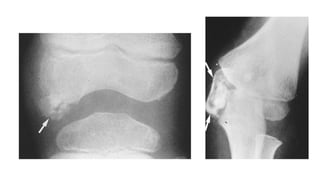

• Double-layered patella as seen on a lateral X-ray of knee is

considered highly pathognomic of EDM

• Double-layered patellaas seen on a lateral X-ray of knee is considered highly pathognomic of EDM

• The fragmentation and deformity of the distal tibiae and tarsals is symmetrical.